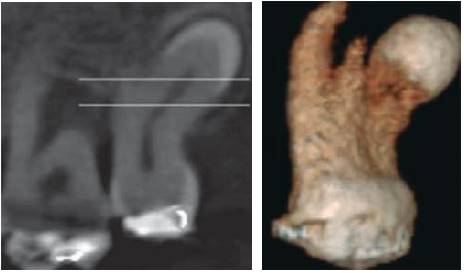

Duarte reported a case of an African American, 47 year old patient, with x-ray evidence of a radiopaque shape with characteristics of cementoblast or fourth molar; exploration clearly stated an inverted distomolar, fused to the palatal root of the third molar, additionally compromising the root canal (Figure 16).15

Cone-beam computerized tomography (CBCT) enables to increase assessment ability in the clinic, with lesser distortion that that obtained with 3D images.55